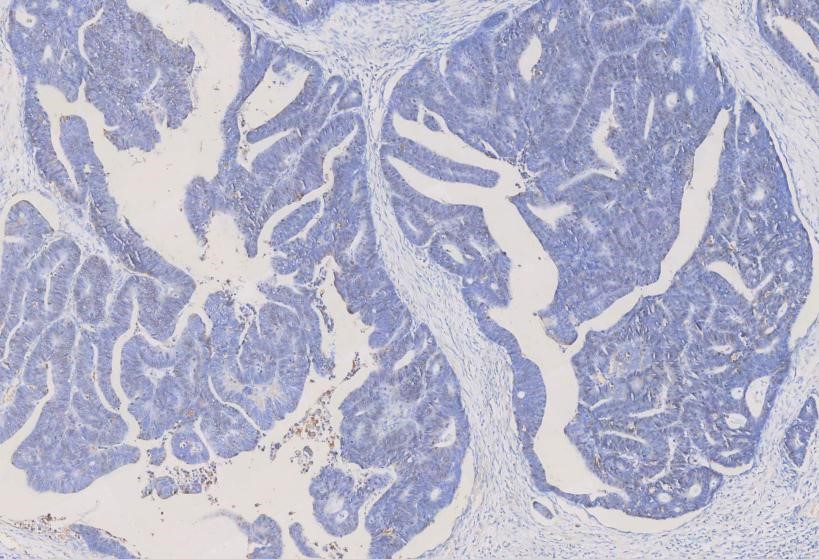

IHC analysis of

Alpha-Smooth Muscle Actin using anti-Alpha-Smooth Muscle Actin antibody

(MA1106). Alpha-Smooth Muscle Actin was detected in a paraffin-embedded section

of human rectal cancer tissues. The tissue section was blocked with 5% BSA. The

tissue section was then incubated with 1μg/ml mouse anti-Alpha-Smooth Muscle

Actin Antibody (MA1106) overnight at 4°C. Peroxidase Conjugated Goat Anti-Mouse

IgG was used as secondary antibody and incubated for 30 minutes at 37°C. The

tissue section was developed using HRP Conjugated Mouse IgG Super Vision Assay

Kit (Catalog # SV0001) with DAB as the chromogen.